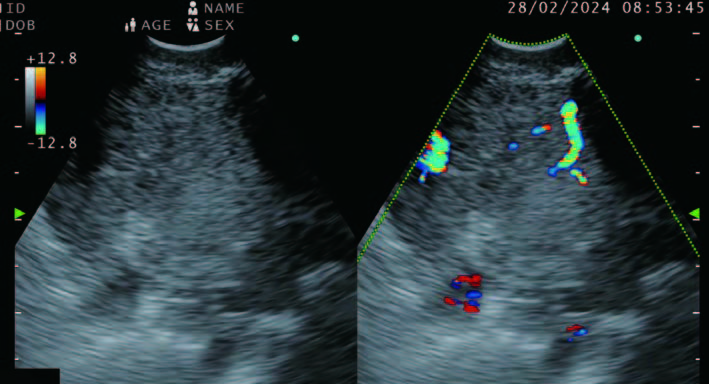

Flow mode in EU-ME3

Figure 3 - Color flow view of intranodal vessels seen alongside the corresponding B-mode view.

The doppler in the new processor comes in three modes. The color flow, power flow and the H-flow mode. The contrast seems better and the intranodal vessels are visualized clearly. We are also able to have the doppler super imposed and corresponding B-mode side by side and thus the poor visibility that we used to have with the previous processors when the doppler was on as the needle enters the node is no longer an issue (Figure 3).